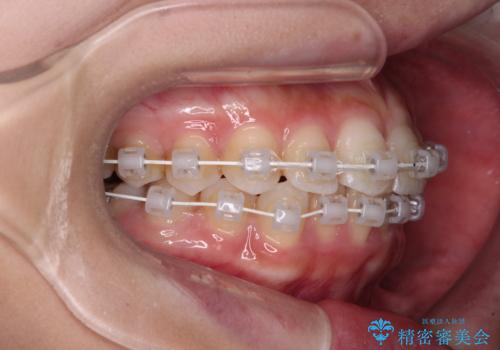

- 矯正装置

- 審美装置

楽して短期間で歯列を整えたいとのことで、ワイヤー装置を用いて矯正治療を行い、矯正治療後に下顎の虫歯はセラミックインレー、上顎はPGAインレー(ゴールドインレー)、根管治療を行う歯についてはオールセラミッククラウンにて補綴治療を行うこととしました。

矯正治療は8ヶ月ほどで終了し、速やかに虫歯治療に移行することができました。